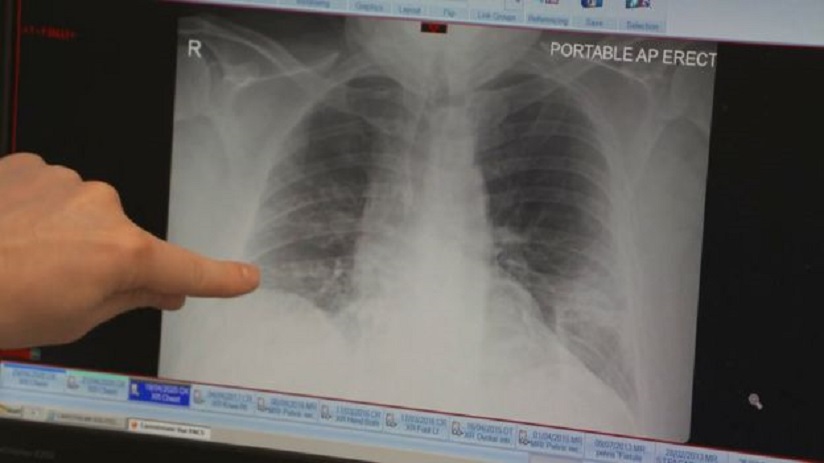

L'étude est dirigée par le professeur James Chalmers, qui est également consultant respiratoire à plein temps chez Ninewells. Il nous a montré une radiographie d'un patient qui a été traité à l'hôpital.

"Nous sommes préoccupés, dans la profession, par le fait que nous voyons apparaître une nouvelle affection pulmonaire, à savoir une maladie pulmonaire post-covid. Il y a une petite proportion de patients qui se retrouveront avec des maladies pulmonaires chroniques à la suite de l'infection au coronavirus et qui auront besoin d'un traitement" dit il.

"Nous aurons donc besoin des cliniques et des spécialistes pour s'occuper de ces patients et leur fournir des soins de longue durée".